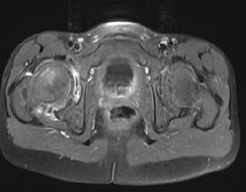

Imaging of Osteochondritis: About 7 Cases and Literature Review

S Habib Chorfa, N Amsiguine, B Bequali, B Dghoughi, N Allali and L Chat S El Haddad. 12(6): 30-34.